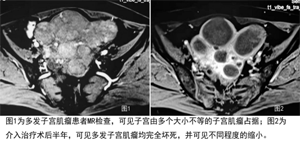

经过准备,医生在局麻下经桡动脉途径,为她实施了子宫动脉栓塞术,仅一个小时手术就顺利完成。术后,罗女士自行走回病房,2天后出院,症状明显好转。6个月后复查,她体内的子宫肌瘤已坏死萎缩。

3.对多发性肌瘤的治疗优势明显。多发子宫肌瘤患者常需切除子宫,这种患者若不切除子宫,手术治疗后往往会在短期内复发。介入治疗则不然,无论肌瘤有多少,只要对子宫肌瘤供血动脉进行彻底栓塞,复发率极低。